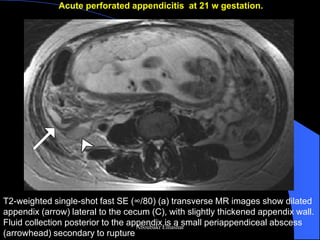

Acute perforated appendicitis at 21 w gestation.

T2-weighted single-shot fast SE (∞/80) (a) transverse MR images show dilated appendix (arrow) lateral to the cecum (C), with slightly thickened appendix wall. Fluid collection posterior to the appendix is a small periappendiceal abscess (arrowhead) secondary to rupture

T2-weighted single-shot fast SE (∞/80) coronal MR images dilated appendix (arrow) lateral to the cecum (C), with slightly thickened appendix wall. Fluid collection posterior to the appendix is a small periappendiceal abscess (arrowhead) secondary to rupture